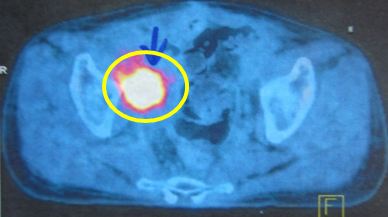

Bệnh nhân được chỉ định chụp PET/CT toàn thân có mô phỏng với kết quả hai khối tổn thương tăng hấp thu FDG mạnh với SUV tăng rất cao vùng hố chậu bên phải:

Hình ảnh PET/CT cắt ngang tiểu khung: Tổn thương vùng hố chậu phải